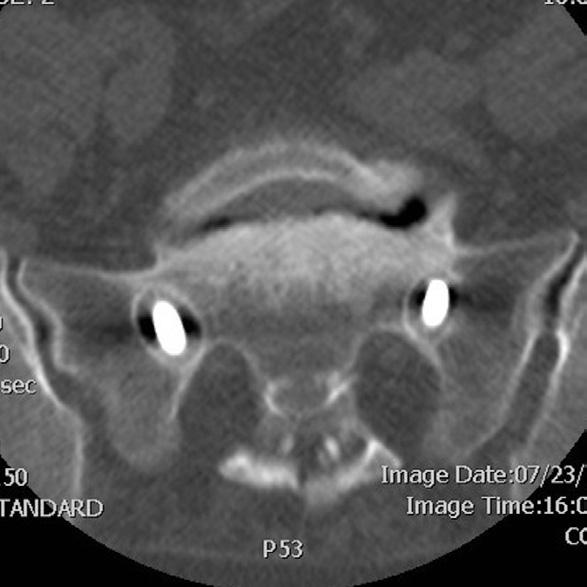

Figure 3. Postoperative sagittal (A) and coronal (B) computed tomography images confirm satisfactory cage placement consistent with preoperative planning.

Figure 2. (A) Design of a personalized interbody cage at L4-5 based on preoperative computed tomography imaging. (B and C) Postoperative radiographs demonstrating ideal cage placement.